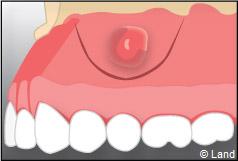

La guérison des sites chirurgicaux péri-apicaux sera suivie par des contrôles cliniques et radiographiques, dans les mois qui suivent.